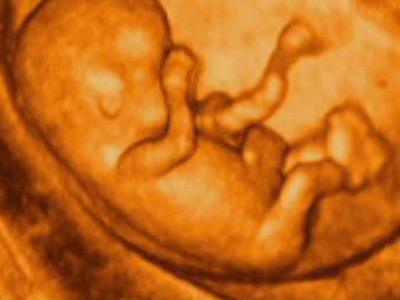

相信各位准妈妈在每次产检的时候,都有类似抑制不住的冲动,想要询问医生:宝宝多重了?是不是健康?是男孩还是女孩?

今天呢,咱们不用问医生,拿起自己的彩超单,自己对照数据,就可以计算宝宝体重了!

一般来说,彩超单上都会显示双顶径(BC)和股骨长(FL)数据。有了这两个数据,就可以轻松应对这两项难题了!不过有个前提,就是生物学孕周与彩超单孕周一致,如果胎儿偏大或者偏小就不适用了。